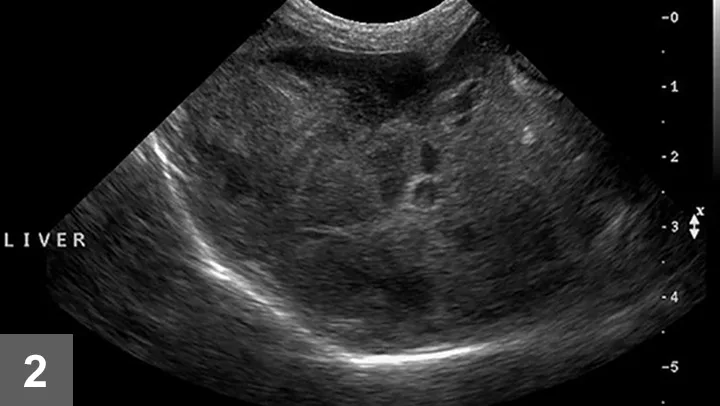

• Ultrasonography is generally the preferred diagnostic imaging modality for evaluation of the liver, and it is particularly useful for mucoceles.

• The normal liver has a homogenous echogenicity that is isoechoic to slightly hyperechoic to the renal cortex.

• Changes in hepatic echogenicity occur in acute and chronic liver disease (Figure 2).

• Ultrasonographic changes are usually not specific for a particular disease.

• The liver can also appear ultrasonographically normal, even in severe disease.

• Ultrasonography is useful for examination of the biliary system, including gallbladder size, contents, and wall thickness, as well as for the intra- and extra-hepatic bile ducts.

FIGURE 2 Ultrasonographic image demonstrating a diffusely mottled and nodular appearing hepatic parenchyma.